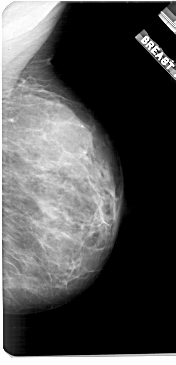

ics_version 1.0 filename A-1921-1 DATE_OF_STUDY 7 6 1994 PATIENT_AGE 36 FILM FILM_TYPE REGULAR DENSITY 4 DATE_DIGITIZED 22 6 1999 DIGITIZER HOWTEK 43.5 SEQUENCE LEFT_CC LINES 5011 PIXELS_PER_LINE 2851 BITS_PER_PIXEL 12 RESOLUTION 43.5 OVERLAY LEFT_MLO LINES 5371 PIXELS_PER_LINE 3076 BITS_PER_PIXEL 12 RESOLUTION 43.5 OVERLAY RIGHT_CC LINES 5131 PIXELS_PER_LINE 2551 BITS_PER_PIXEL 12 RESOLUTION 43.5 NON_OVERLAY RIGHT_MLO LINES 5461 PIXELS_PER_LINE 2626 BITS_PER_PIXEL 12 RESOLUTION 43.5 NON_OVERLAY |